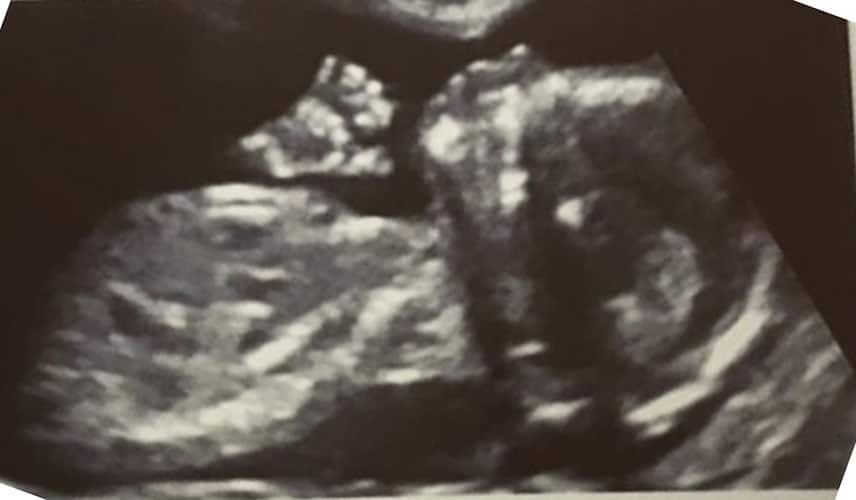

Ultraschallbilder aus dem 2. Trimester (13. bis 28. SSW)

Im 2. Trimester bekommt man oft die schönsten "Ganz-Körper" Ultraschallbilder. Das Baby ist nun so groß, dass man alles gut erkennen kann und noch nicht zu groß, so dass es noch ganz auf das Bild passt. In dieser Zeit lässt sich meist das Geschlecht bestimmen, wobei manche Babys es einfach nicht preis geben wollen und sich immer so drehen, dass man nichts erkennen kann.